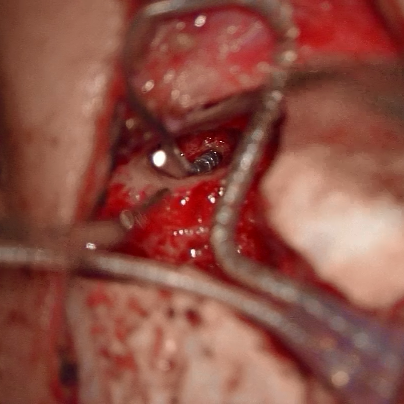

中耳炎人工听骨植入重建听力 人工耳蜗植入